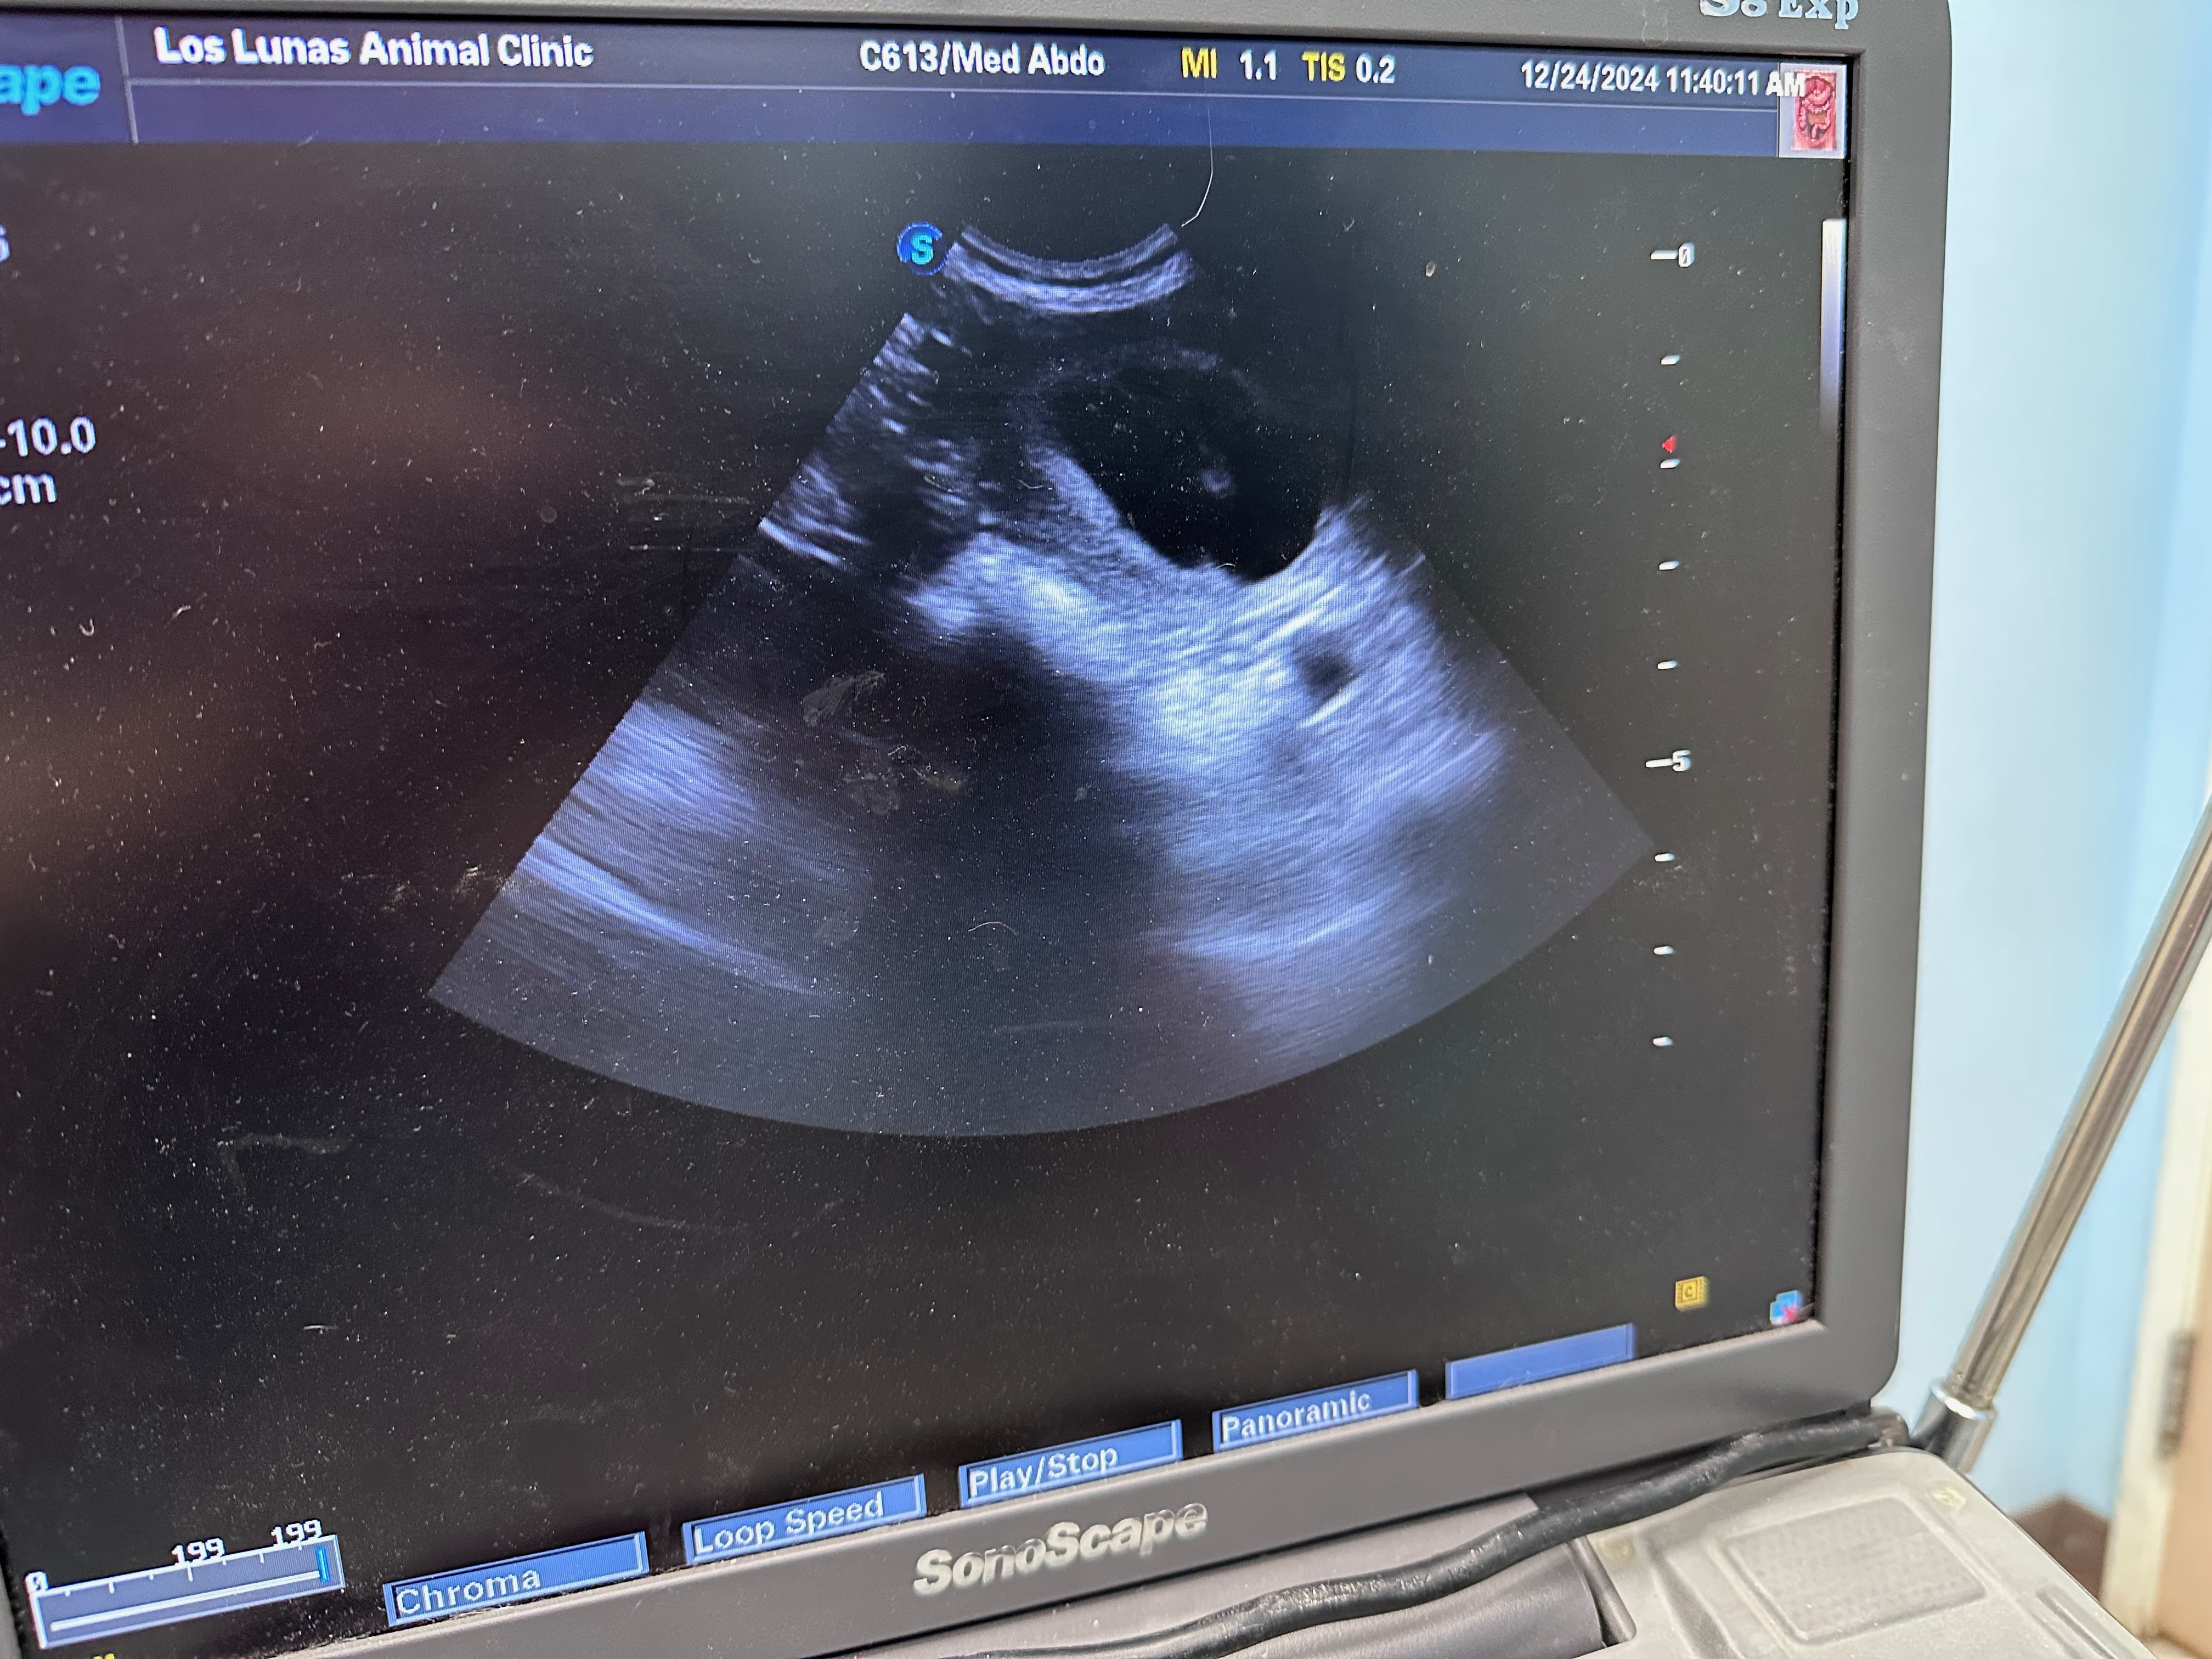

December 24, 2025 Ultrasound at Los Lunas Animal Clinic, Los Lunas, New Mexico PREGNANT!!!